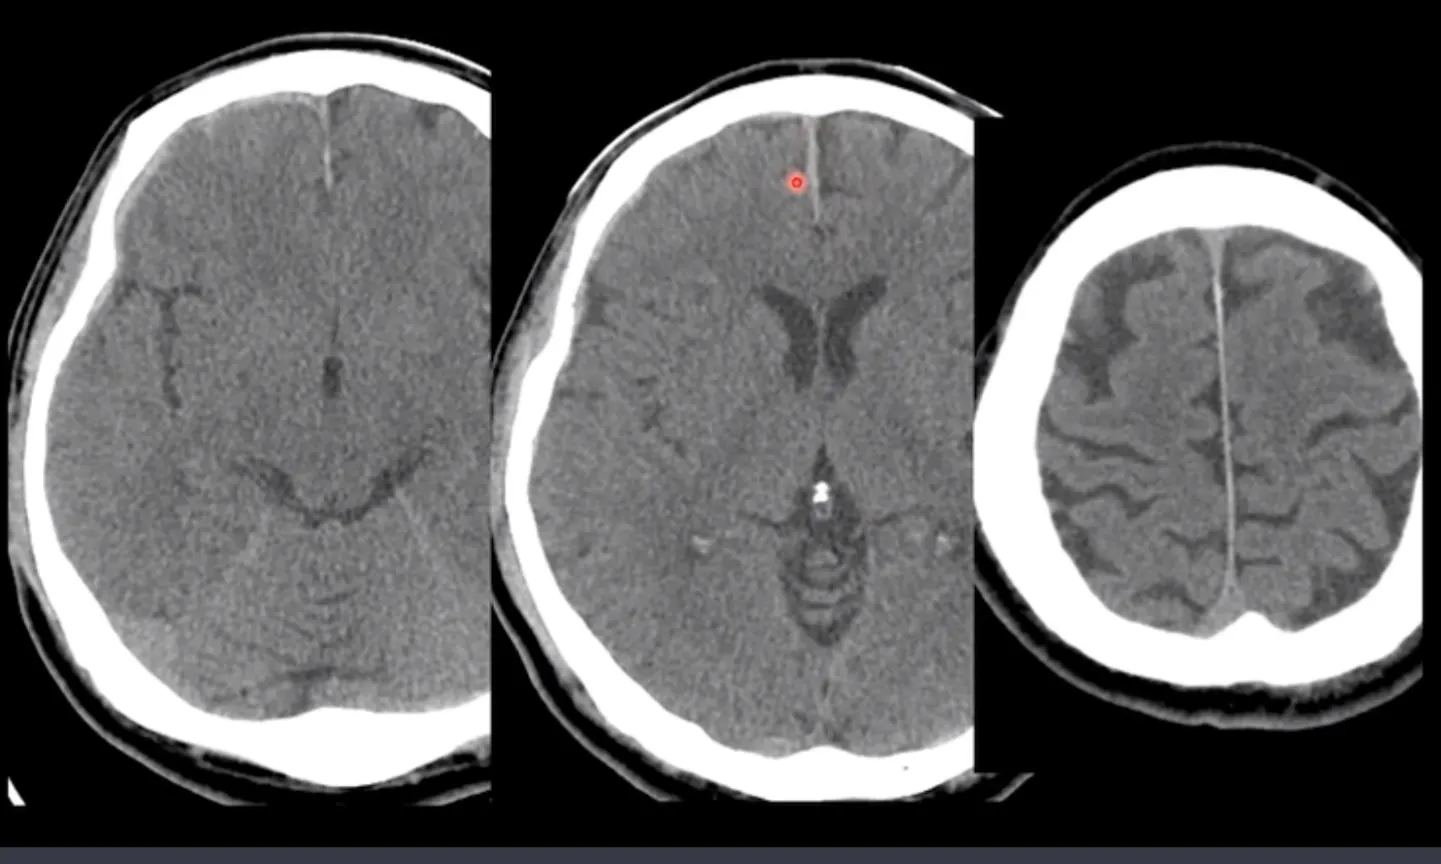

(해설) 아래 사진은 SDH 중에서 falx의 출혈 사진입니다. Rt fronto temporal 로 thin SDH가 보이는데, Falx 도 두꺼워져 보이면서 가운데 확대사진을 보면 경계가 울퉁불퉁해 보입니다. 이러면 출혈 가능성이 높습니다. 반면 가장 오른쪽 사진처럼 falx의 density가 올라갔지만 두께는 더 얇아지고 경계가 매끈하다면, 정상일 가능성이 높습니다. falx에는 정상적으로도 calcification이 잘 됩니다. 하지만 완전한 감별은 어려우므로 f/u을 하는 게 좋습니다.

좌측: Rt frontal SDH가 interhemispheric fissure까지 연장된 사진

중간: Falx 앞쪽이 두껍고 경계가 울퉁불퉁함 → SDH로 보임

우측: 같은 환자의 더 윗 레벨. falx density는 더 올라갔으나 경계가 매끈하고 두께가 얇음. 정상추정

(해설) subtentorial SDH는 우측 상단그림처럼 양이 많은 경우라면 발견이 쉽지만 적은 경우는 애매한 경우가 있습니다, 가능성이 있다고 판단되면 F/U CT 촬영을 해 보면 됩니다.